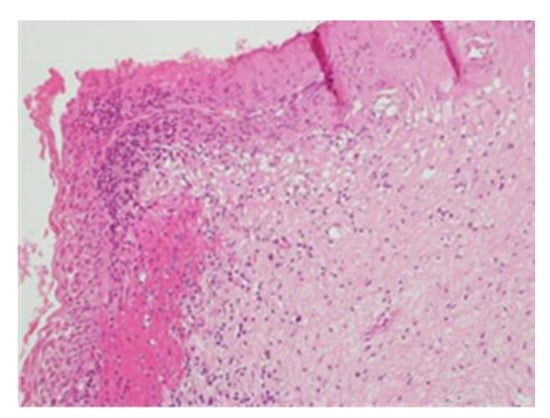

Figure 4.

CIN3 histological sample of the left enlargement margin; also, in this case, enlarged and hyperchromatic nuclei, clumped chromatin, irregularities and indentations in the nuclear membrane, and an altered nuclear/cytoplasmic ratio are observed.